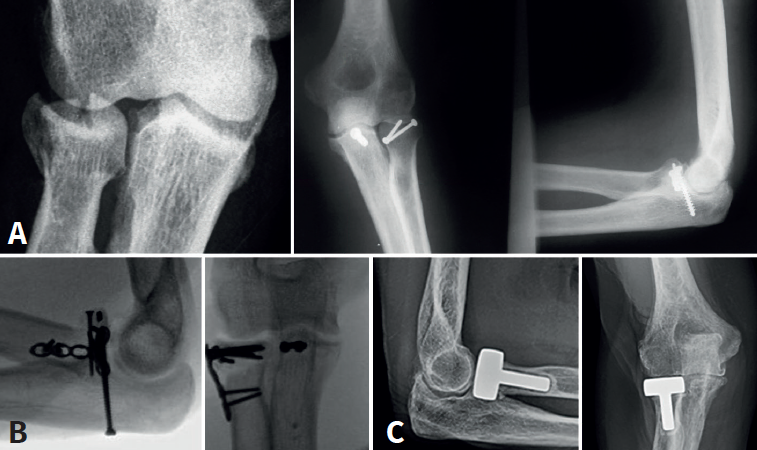

El tratamiento de la fractura de la cabeza radial es crucial para la estabilidad lateral del codo(12). El manejo depende del grado de conminución; en nuestro caso nos basamos en la clasificación de Mason (1954) y Johnston (1952)(13):

- Mason I: son aquellas fracturas sin desplazar o mínimamente desplazadas (< 2 mm) y sin bloqueo mecánico en la pronosupinación. El manejo adecuado sería conservador. En aquellos casos en los que exista un fragmento óseo (< 20%) que podría comprometer la recuperación postoperatoria se podría optar por una resección de este.

- Mason II: fracturas desplazadas > 2 mm o anguladas, y que podrían presentar un bloqueo mecánico a la rotación del antebrazo. Se opta por un tratamiento quirúrgico mediante reducción abierta y fijación interna con tornillos canulados o placas bloqueadas de bajo perfil(14).

- Mason III: fracturas conminutas, desplazadas, con bloqueo mecánico a la rotación y potencialmente irreparables. La fijación de aquellas fracturas de la cabeza del radio en 3 partes (diáfisis y 2 fragmentos articulares) es propensa a un fracaso temprano de la fijación, a una falta de consolidación y a una rotación limitada del antebrazo(15). Es por ello por lo que, en estos casos, puede ser preferible la resección de la cabeza radial seguida de la colocación de una prótesis modular. Doornberg et al.(16) han sugerido que el borde lateral de la coronoides es un punto de referencia útil para dimensionar la cabeza del radio y, en general, la prótesis no debe quedar más de 1 mm proximal a este punto de referencia (Figura 5).